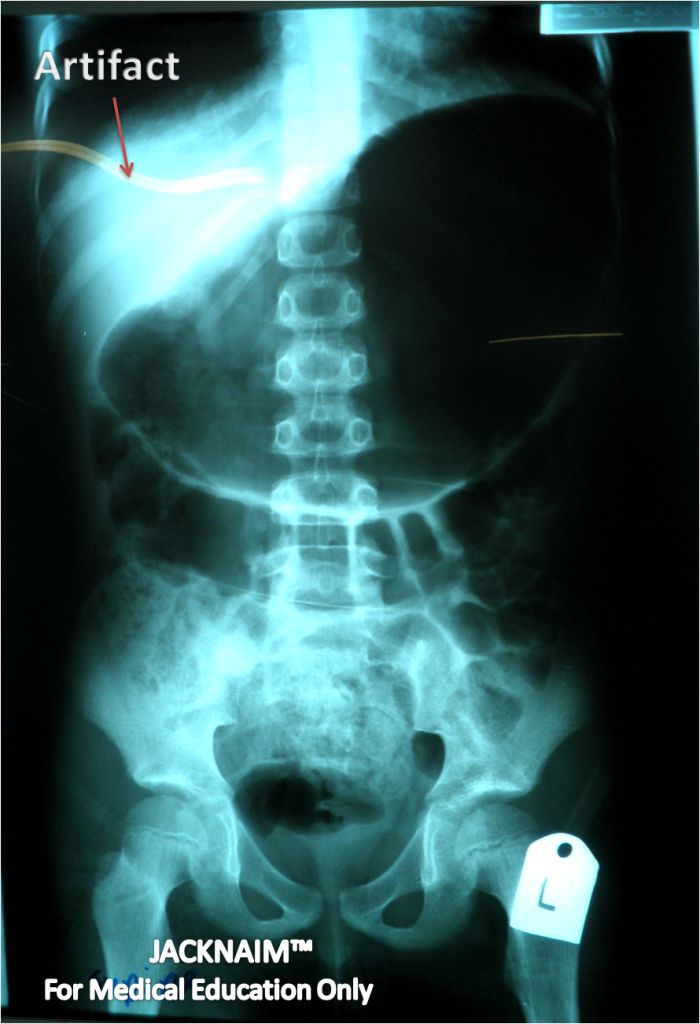

8 years old malay boy was brought to casualty with GCS 7 (E1, V1, M5) after being hit by a car and was intubated to protect the airway. On examination, there was a nose bleeding, laceration wound of the face and distended abdomen. X ray of the skull, cervical, chest, abdomen and pelvic was taken. Below is the film of abdomen and pelvis x-ray.

1) Mention your finding based on the two x ray (2m)

2) What is your radiological diagnosis (1m)

3) Outline your management to this patient (2m)